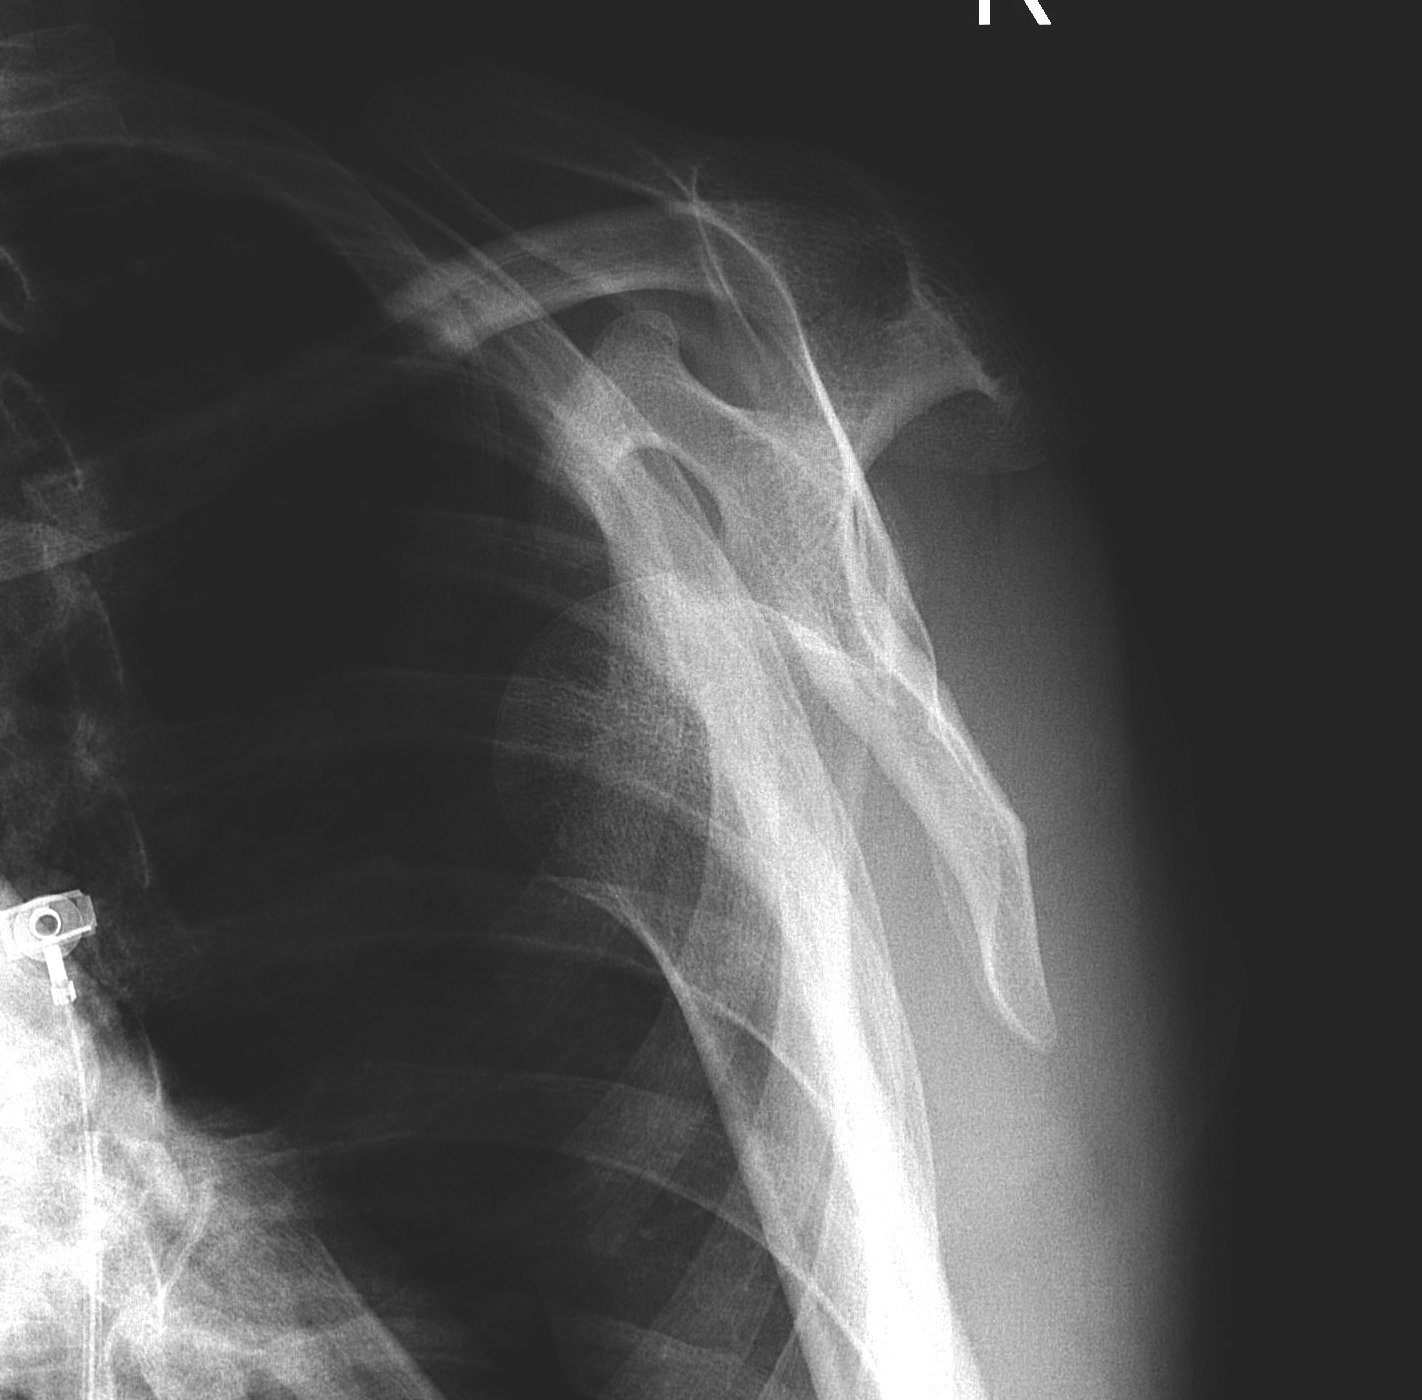

Greater tuberosity fractures

Indications

- > 5 mm displacement

Management

- ORIF with plate

- screw + suture repair

- screw alone in young patient